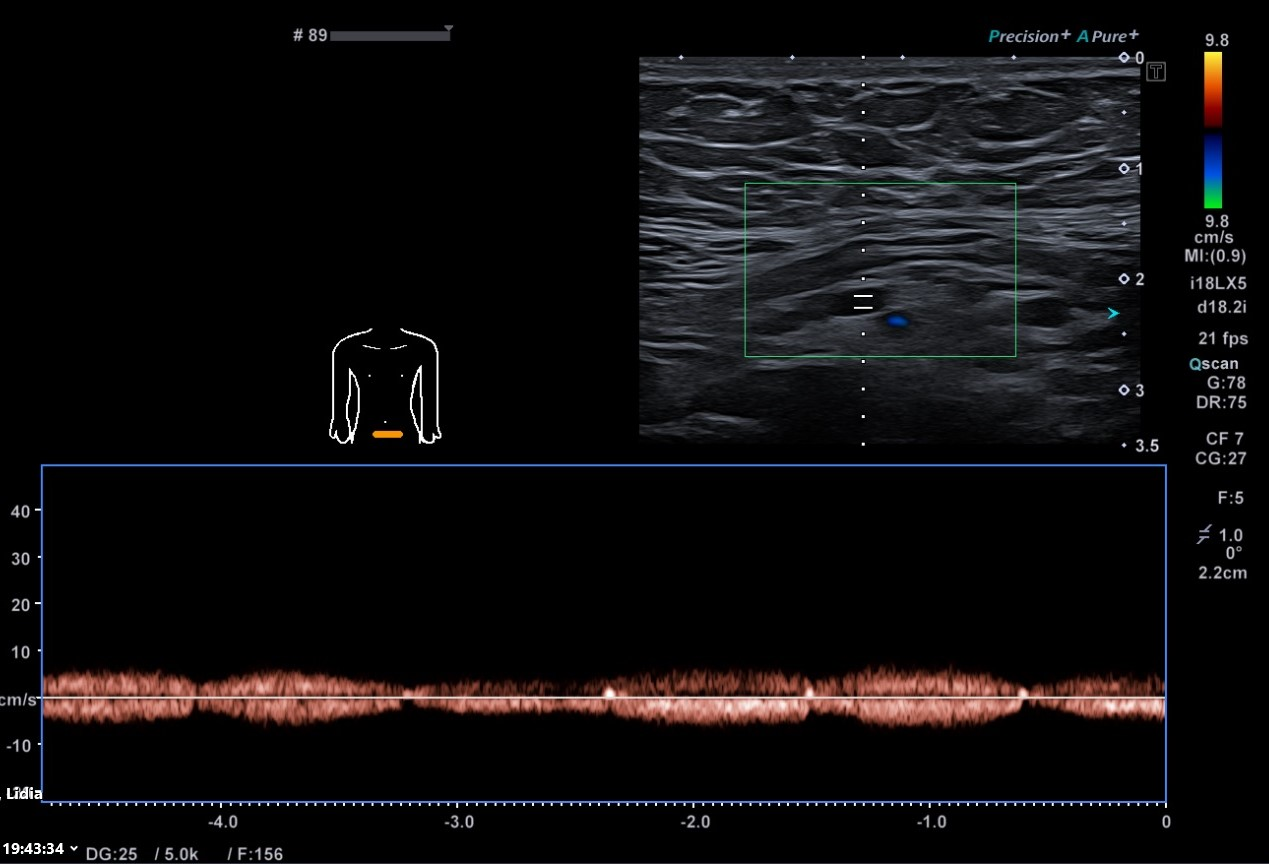

Ecografía partes blandas: En localización infraumbilical, sin aparente dependencia de estructuras profundas ni modificación en maniobra de Valsalva, lesión hipoecoica bilobulada (4,3 x 8,5 x 7,1 mm) con aparente conexión hacia región vesical, sobre la que no se demuestra vascularización, inespecífica, que podría corresponder a seno uracal, sin poder descartar sobreinfección asociada.